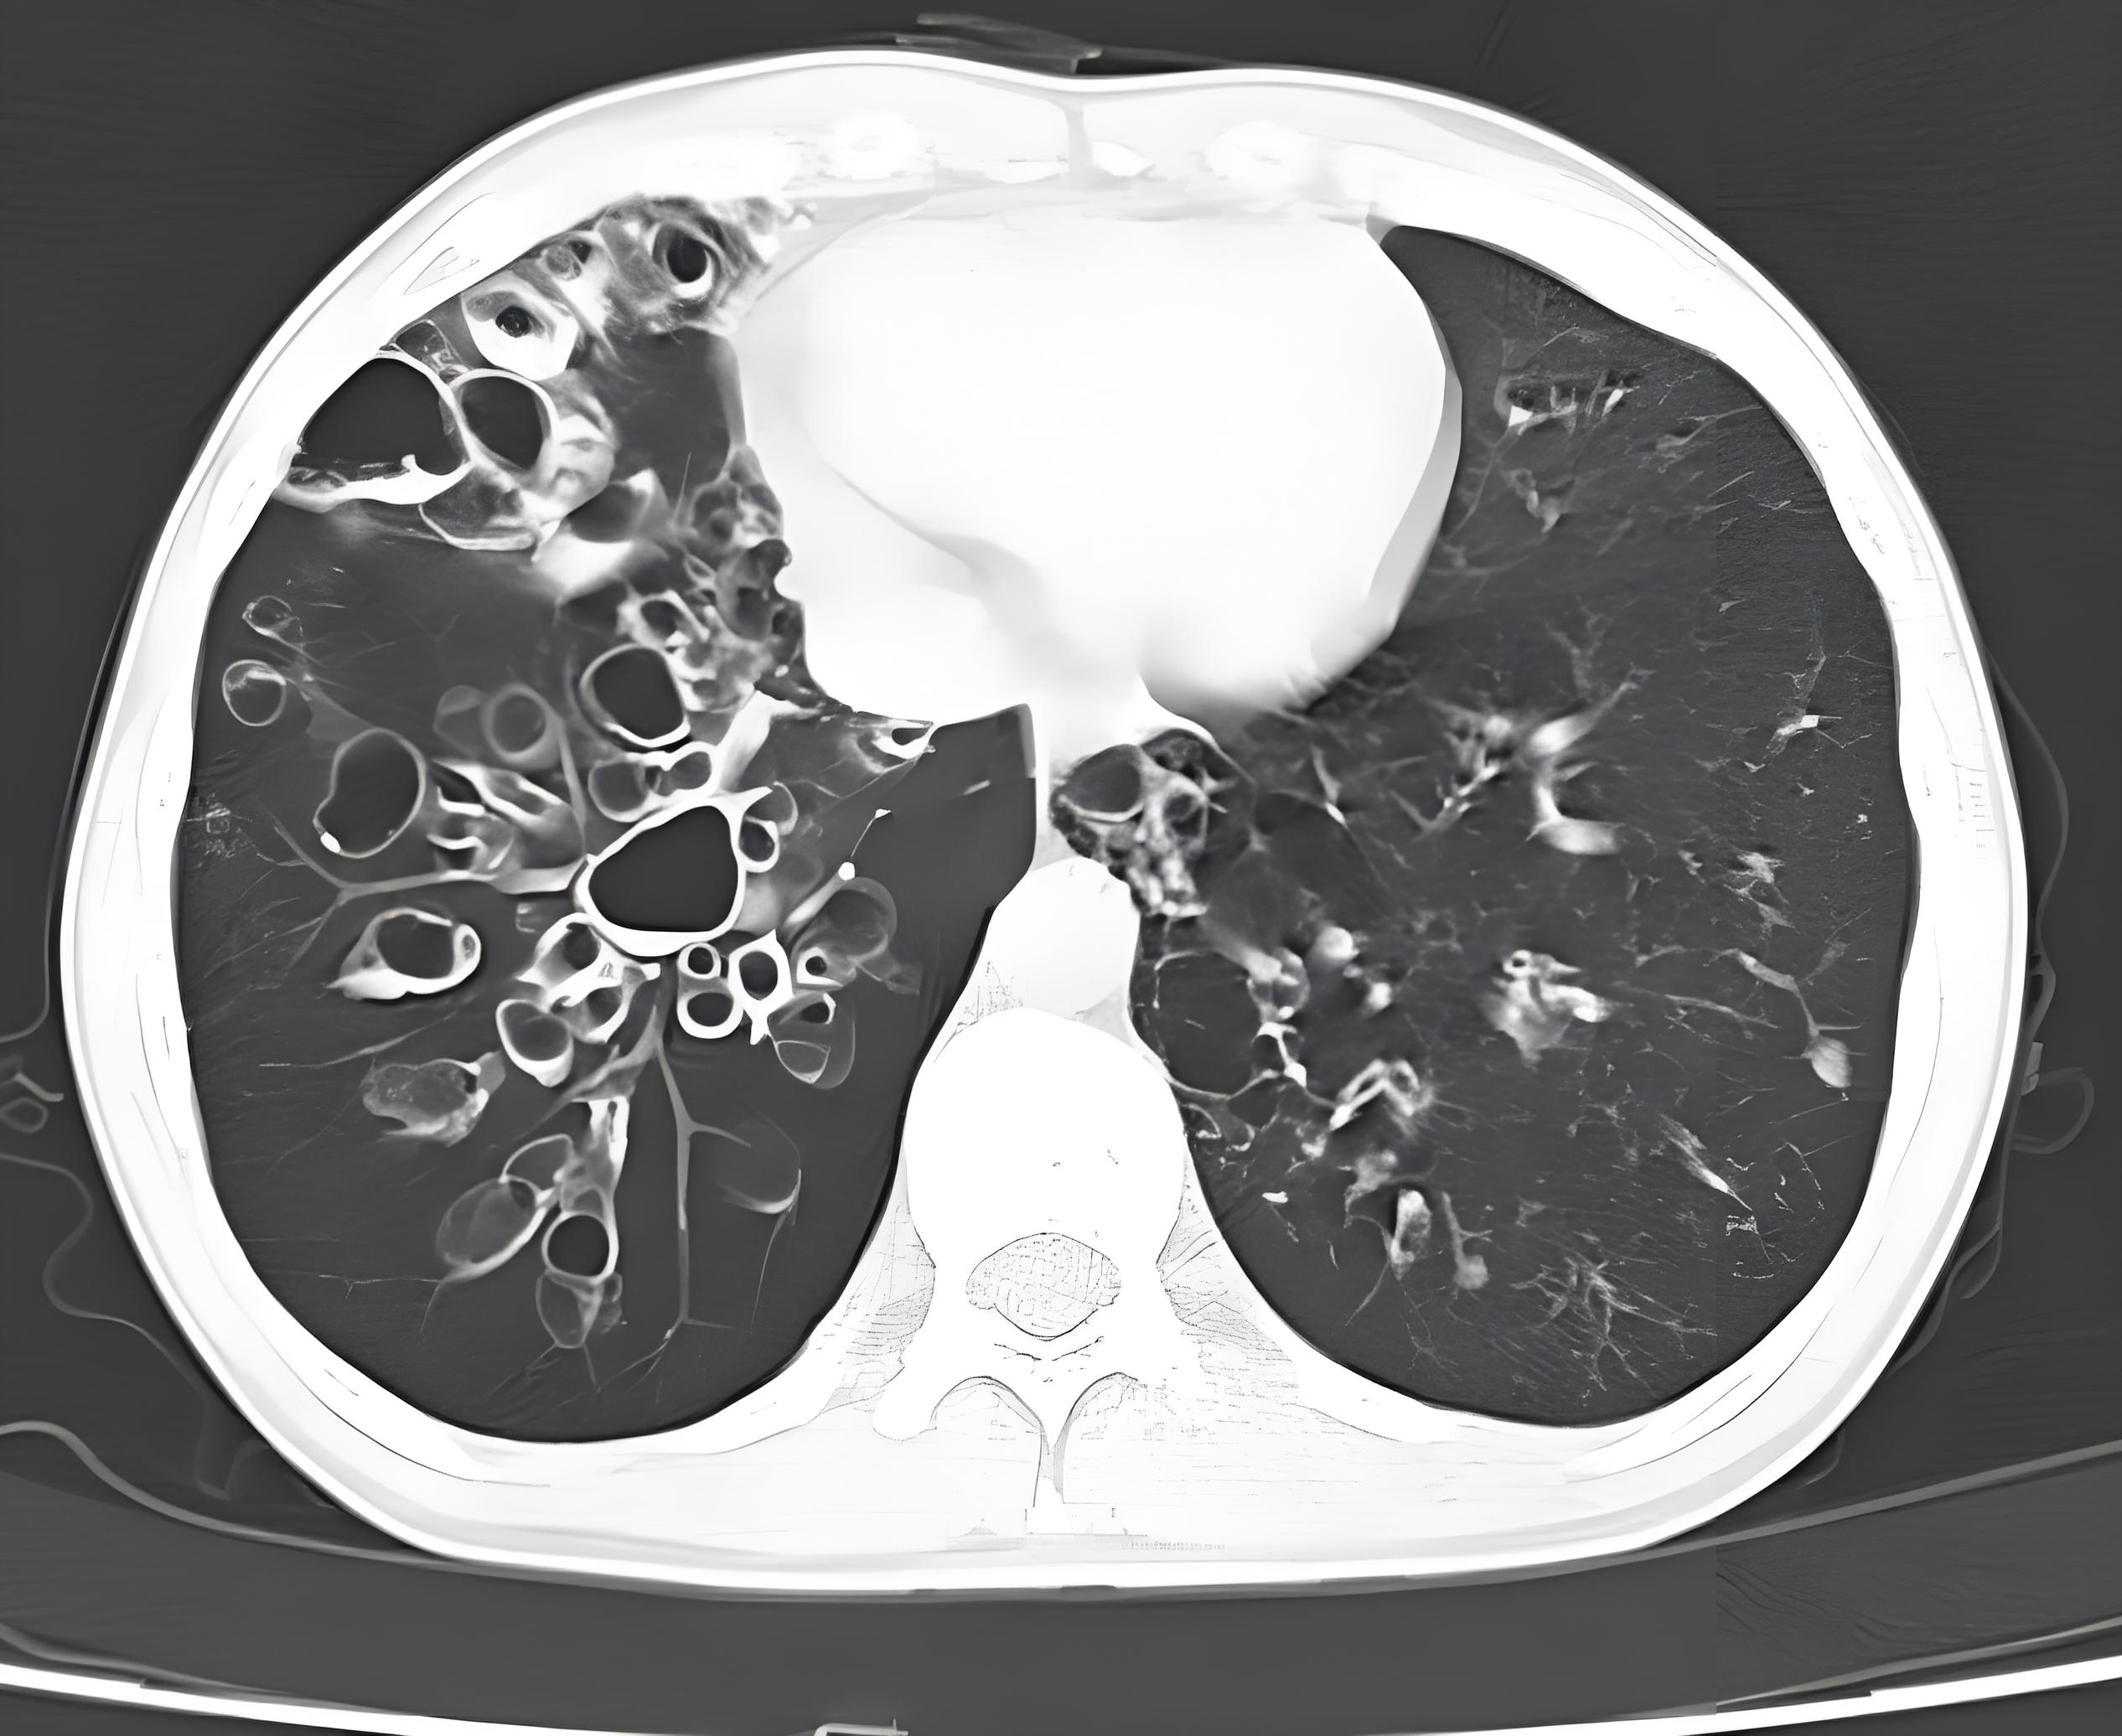

双肺纹理增多 影像显示肺部血管和支气管纹理较正常更为密集,可能与

入院后,查胸部增强ct提示典型的蝴蝶症

前一天胸片只提示双肺纹理增多,今天住院查肺ct提示重症肺炎,左肺肺实